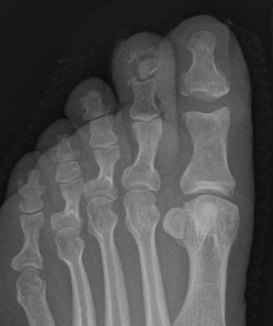

Interphalangeal joint dislocation

Pathology

Hyperdorsiflexion

P1 head dislocates plantar

Fractures

Xray